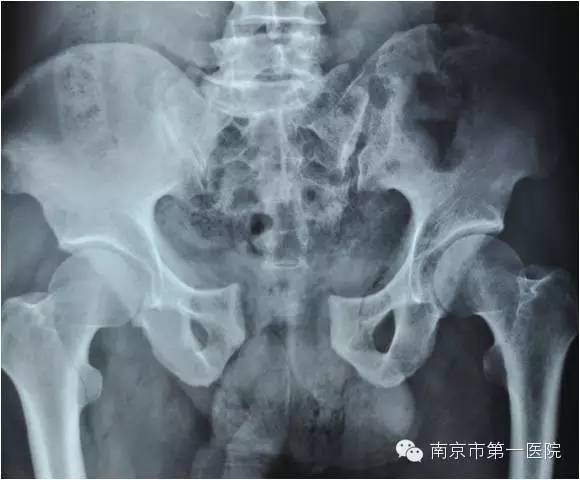

随后,老张第一时间被送到当地医院进行了简单处理,处理完又立刻转到南京市第一医院进行进一步抢救。据了解,小卡车大约1.5吨重,受伤的部位在骨盆,由于受到碾压和挤压,导致骨盆内的肌肉撕裂、血管损伤,骨盆也粉碎性骨折。另外,同时存在右侧胫腓骨粉碎性骨折及大面积软组织损伤。

据了解,骨盆骨折是一种严重外伤,占骨折总数的1%~3%,多由高能外伤所致,半数以上伴有合并症或多发伤,致残率高达50%~60%。因此,在对患者进行输血、补液、液体服务等抗休克治疗的基础上,ICU立即组织院内骨科专家进行会诊。

我院骨科专家梁斌接到通知后,开通多发伤绿色通道,迅速召集科内骨干医生进行术前讨论、制定手术计划。考虑到患者创伤严重、出血量大,必须最大程度地减少手术伤口,梁主任决定立刻采取微创技术进行骨盆闭合复位支架外固定术。